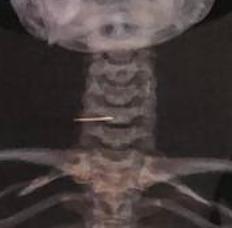

[鱼骨致颈动脉穿孔——一例报告]

[[Carotid artery perforation by fish bone - a case report]].

Accidental fish bone ingestion is a common complaint at emergency departments. The majority of cases have a benign course. However, serious complications such as esophagus perforation, cervical vessel injury and cervical abscess can occur in 7.4% of cases. Mortality rates can be as high as 50% when mediastinitis occurs. We report a case of an esophageal perforation caused by a fish bone with a lesion to the right common carotid artery after 20 days of evolution. Surgical exploration occurred with corrections of the lesion in the right common carotid and esophagus. Early identification of this kind of injury is paramount to prevent potentially fatal complications.

摘要

意外吞食鱼骨是急诊科常见的就诊原因。大多数病例病程良性。然而,7.4%的病例可能会出现严重并发症,如食管穿孔、颈血管损伤和颈部脓肿。发生纵隔炎时死亡率可高达50%。我们报告一例鱼骨导致食管穿孔的病例,病程20天后右侧颈总动脉出现损伤。进行了手术探查,修复了右侧颈总动脉和食管的损伤。早期识别此类损伤对于预防潜在的致命并发症至关重要。